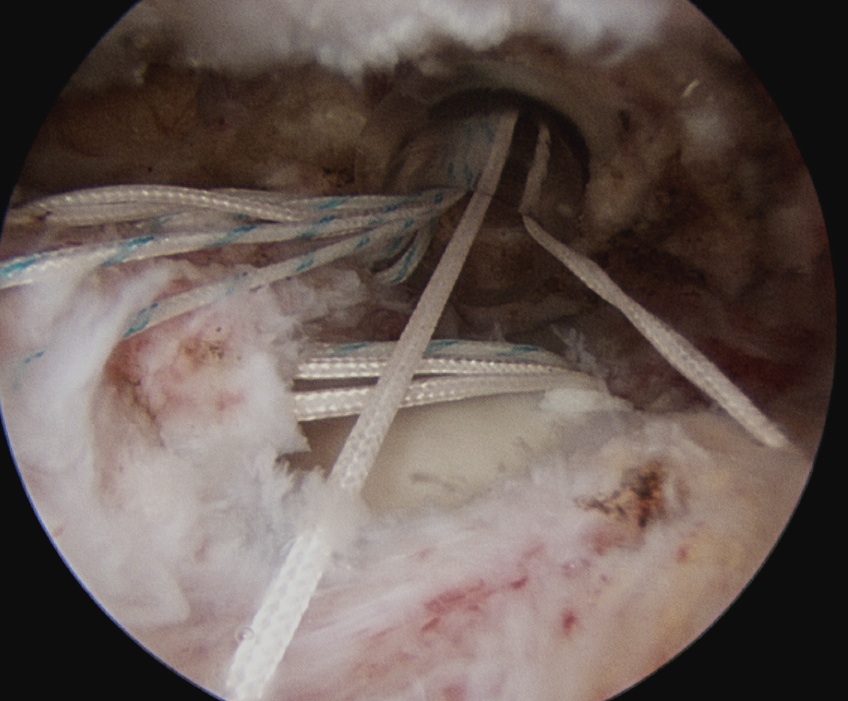

D. Transosseous equivalent / suture bridge

Technique

- biomechanically replicate tradional open transosseous

- sutures crossed as below in double row

- aiming to increase contact between cuff and footprint

Double row

- either pass second lateral row of anchors or

- use foot print anchors, retrieve previous sutures

- can make suture bridge configuration

- check repair via lateral portal